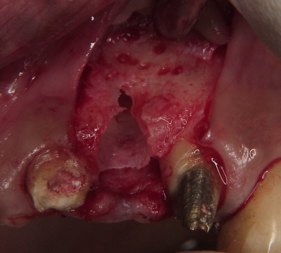

歯茎を開いて骨面を露出させます。

術前に十分な診査・検討を行い

適切な位置と長さに穴を開けていきます。

インプラントを埋入します。

全部で5本のインプラントが見えます。

右下は既に使っています。